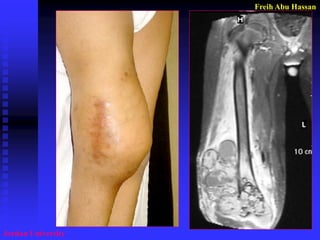

Poor & Bad biopsy

1.Taking Bx. away of the site

of possible future Surgery

3. Hematoma  spread of tumor cells.

4. large incision Open Bx.

Bx were performed through a large incision with contamination of tissues. !!!!!!!